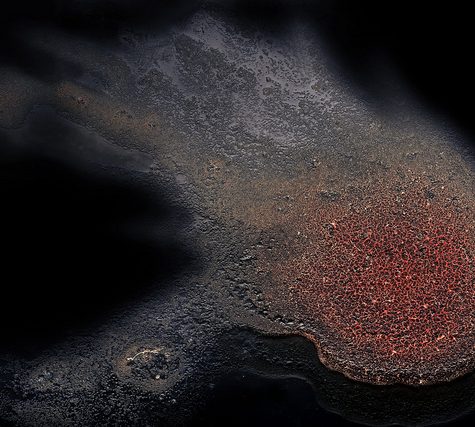

Red blood cells (RBCs), also called erythrocytes, are the most common type of blood cell and the vertebrate organism’s principal means of delivering oxygen (O2) to the body tissues—via blood flow through the circulatory system] RBCs take up oxygen in the lungs or gills and release it into tissues while squeezing through the body’s capillaries. They are between 6-8 microns in diameter.

The cytoplasm of erythrocytes is rich in hemoglobin, an iron-containing biomolecule that can bind oxygen and is responsible for the red color of the cells. The cell membrane is composed of proteins and lipids, and this structure provides properties essential for physiological cell function such as deformability and stability while traversing the circulatory system and specifically the capillary network.

In humans, mature red blood cells are flexible and oval biconcave disks. They lack a cell nucleus and most organelles, in order to accommodate maximum space for hemoglobin. Approximately 2.4 million new erythrocytes are produced per second in human adults. The cells develop in the bone marrow and circulate for about 100–120 days in the body before their components are recycled by macrophages. Each circulation takes about 20 seconds. Approximately a quarter of the cells in the human body are red blood cells.